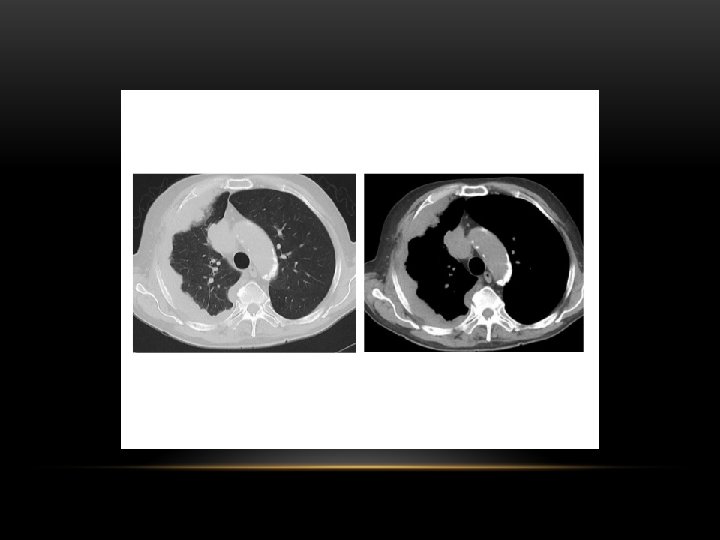

CT scan of left empyema with pleural enhancement

loculated pleural effusion